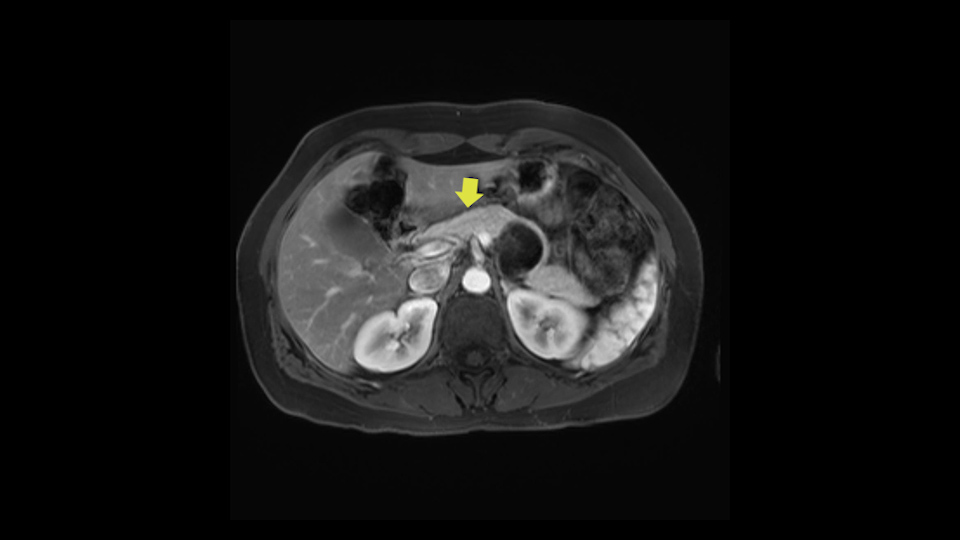

Additional slowing down moments are: division of the neck of the pancreas - to ensure that you obtain an adequate margin within the pancreas.

The slowing down moments or considerations that I give when I look at the scan and plan my distal pancreatectomy is how far away the tumor is to the portal vein and do I have to formally create a tunnel behind the pancreas on top of the portal vein or do I have to take the pancreas further to the left of the portal vein or the patient’s left of the portal vein. So here I can see that here is the tumor here. I can see that the tumor is a fair way away to the patient’s right and so I will likely not have to take or create the tunnel formally in this procedure. And that speaks a lot to the resection margins. So its important when you’re doing a distal pancreatectomy or any procedure potentially for oncologic reasons to get clearance of the tumor and to take the tumor kind of intact.

I mentioned earlier that transection at the neck is the area that I would normally do as long as I have good margin from the lesion. And if the margin is not enough, I would go further to go to the right of the PV-SMV area at the junction and do the transection at that point.

Key features that I look at the imaging are: first I look at the distance between the cyst and the portal vein SMV confluence. So there are guidelines for this, they call the Yonsei guidelines, to decide to do it laparoscopically or open and basically it says that if it’s a cancer, at least a centimeter away from the celiac trunk or the venous confluence. This is a cyst. So maybe you could stretch that a bit, but you don't want to get into trouble there. So for this cyst if you look at it, it's nicely away from the confluence.

So unfortunately I cannot show you a coronal view but you can see it easily on this scan, going down first you see the celiac trunk and you see here, quite a nice distance between the celiac trunk and the beginning of the mucinous cyst. And if you go up here and follow down the portal vein confluence you also see a nice distance there.

Moving down to the right, you will encounter the superior mesenteric vein. Definitely a slowing down moment. And that's when you can start to make the beginning of a tunnel. You don't make the entire tunnel. Then you go to the cranial side of the pancreas. Also there you mobilize it fully. The slowing down moment is freeing the hepatic artery and the station 8 lymph node which is there which comes with a routine oncologic resection so you mobilize that off the hepatic artery and then you continue at the superior side of the pancreas, going up to the celiac trunk, taking also the lymph nodes on the left gastric artery and below the celiac trunk. After you've done that, you can complete the tunnel and also hang the pancreas there with a bit of vessel loop. So basically now you’ve got two vessel loops around the pancreas, you can hang the entire pancreas. From that comes, stapling of the pancreas. I typically do that first before transecting any vessels. You can staple the pancreas with various staplers. Depending on the size, if you cut it at the neck, which you should do for oncologic resection. You could probably take a thinner stapler than if you would go more to the left side of the pancreas. There's no conclusive evidence on which stapler to use.